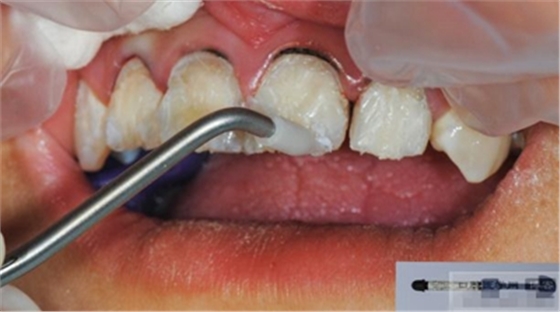

【酸蝕粘結(jié)】

使用磷酸酸蝕可用完全去除玷污層,粘結(jié)劑可用充分滲透到牙本質(zhì)小管中。用自酸蝕系統(tǒng)則達(dá)不到這一點(diǎn),由于其不能充分去除玷污層,粘結(jié)劑向牙本質(zhì)小管內(nèi)的滲透率低。所有的研究均顯示,使用全酸蝕系統(tǒng)所形成的粘結(jié)混合層要比使用自酸蝕系統(tǒng)厚。

將粘結(jié)劑在牙體硬組織上充分涂布20秒,最少2次,然后,輕輕吹干,固化。理想的粘接劑的厚度不應(yīng)超過(guò)50微米。如果粘接層過(guò)后可能會(huì)發(fā)生微滲漏,過(guò)薄則可能彈性不足。飽和粘接系統(tǒng)第一層厚度可以達(dá)到30-40微米,有時(shí)也會(huì)超過(guò)此值。但這個(gè)厚度對(duì)于一些情況不適用,如嵌體粘結(jié)。80-100微米厚度的粘接層難以形成持久的固位力。電子顯微鏡照片顯示飽和粘接系統(tǒng)會(huì)形成較厚的粘接層,并且,其內(nèi)部充滿氣泡,optibond和PQI就屬于飽和粘結(jié)系統(tǒng)。Dr.Vanini的建議最好使用不飽和粘結(jié)系統(tǒng),因?yàn)?,飽和粘結(jié)系統(tǒng)往往會(huì)形成過(guò)厚的粘結(jié)層。Dr.Vanini使用ENA bond粘接系統(tǒng),在單層應(yīng)用時(shí)厚度為8微米,2層為12微米,3層為25微米。三層粘結(jié)劑所形成的粘接力值可以達(dá)到49MPa(N/平方MM)。使用非飽和粘結(jié)系統(tǒng)進(jìn)行2-3層的粘接方法的另一個(gè)優(yōu)點(diǎn)是可以減少術(shù)后過(guò)敏癥狀的出現(xiàn)。

紙尖拭干

光照強(qiáng)度要達(dá)到800-1000毫瓦。鹵素?zé)舻拇┩噶σ劝l(fā)光二極管強(qiáng)。粘結(jié)嵌體時(shí)要用鹵素?zé)?。常?guī)應(yīng)用發(fā)光二極管燈更加方便。